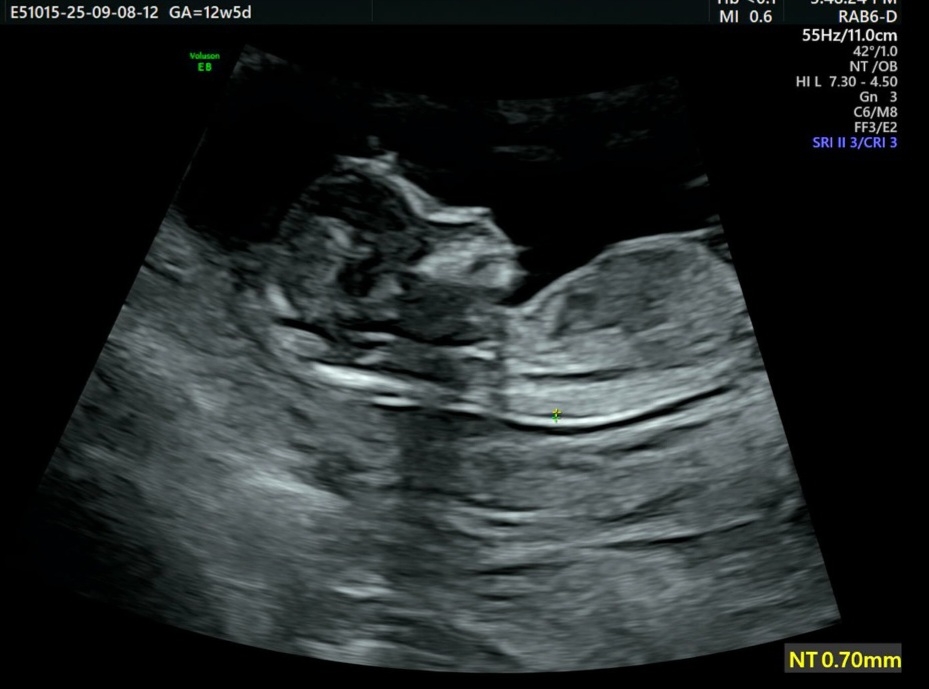

목투명대 재는위치

12주5일 ) 첫째낳고 6년만에 둘째가 왔어요 . 이미 한번 경험은 했지만 오래돼서ㅠ가물가물 하기도하고 ... 이제 노산에 속해서 괜히 걱정도 되어 여기다 물어봐요 . 목 투명대 위치가 저위치도 해당이 되나요 ? 아이가 계속 안보여줘서 한참 헤매다가 재주셨는데 1mm미만은 주변에서도 잘 안들어보고 위치도 첫째는 더 위쪽으로 재주셨었거든요 . 저위치에서 재신분들도 계세요 ?

저도 약간 목 아래쪽 재셨는데 척추까지 이어지는 부분이라 그렇기도 한다고하고, 가장 두꺼운 부분을 여려번 재시더라구요.

0.92mm 였는데 저 위치는 아니었어요

저도 0.9mm나오긴했는데 위치가 이상하긴하네요 다른병원가보셔요!!

안그래도 기간이 더 늦어지면 정확하지 않다해서 좀전에 다른병원 다녀왔는데 다행히 1.12정도 나왔는데 너무 늦게 1차 검사하신거 같다고 하시더라구요 ...